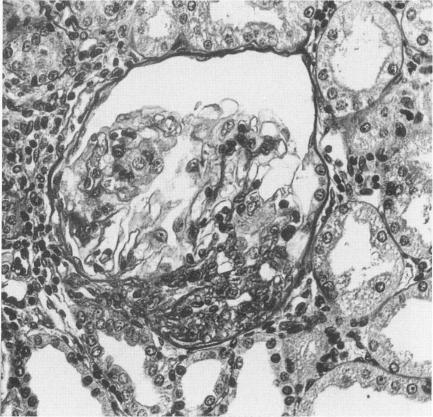

Rats with extensive renal mass reduction develop hypertension, proteinuria and progressive glomerulosclerosis. Previous studies have demonstrated that these changes are associated with an increased urinary excretion of thromboxane compared with normal rats and that the administration of a thromboxane synthetase inhibitor prevents glomerulosclerosis and progressive renal function deterioration. On this basis it has been speculated that the thromboxane synthetase inhibitor, by inhibiting platelet thromboxane, reduces platelet aggregation and prevents the generation of substances that can influence glomerular functional properties. Because the thromboxane synthetase inhibitor also inhibits thromboxane synthesis by resident glomerular cells and lowers blood pressure in these animals, the question of whether platelet thromboxane is indeed the factor implicated in the development of renal disease after renal ablation remains unanswered. To address this issue the authors administered at different time intervals from the surgical procedure a low-dose of oral aspirin (ASA) to rats with remnant kidney. This approach resulted in selective inhibition of platelet cyclooxygenase leading to an almost complete prevention of platelet thromboxane generation. Low-dose ASA spared renal cyclooxygenase as documented by a lack of significant inhibition of glomerular and urinary 6-keto-PGF1 alpha and did not lower blood pressure. Renal function studies showed that low-dose ASA, despite inhibiting platelet aggregation, had no effect on proteinuria and progressive renal insufficiency irrespectively if administered late (ie, 80 days after surgery) and given daily for all the observation period (ie, 20 days) or earlier in the course of the disease (ie, 40 and 10 days after surgery). Histologic data showed that the degree of glomerulosclerosis and tubulo-interstitial damage was not significantly different in rats with reduction of renal mass alone compared with rats with remnant kidney given low-dose ASA. In conclusion, the present findings indicate that inhibition of platelet aggregation and thromboxane formation does not prevent the progressive glomerulosclerosis that develops in rats with surgical reduction of renal mass. It is suggested that the beneficial results obtained previously in the same model by the use of a thromboxane synthesis inhibitor must be attributed either to an effect on resident glomerular cell thromboxane synthesis or to lowering systemic blood pressure.

肾实质大量减少的大鼠会出现高血压、蛋白尿和进行性肾小球硬化。先前的研究表明,与正常大鼠相比,这些变化与血栓素尿排泄增加有关,并且给予血栓素合成酶抑制剂可预防肾小球硬化和肾功能进行性恶化。在此基础上,有人推测血栓素合成酶抑制剂通过抑制血小板血栓素,减少血小板聚集,并防止产生可影响肾小球功能特性的物质。由于血栓素合成酶抑制剂还抑制肾小球固有细胞的血栓素合成并降低这些动物的血压,因此肾切除术后血小板血栓素是否确实是参与肾脏疾病发展的因素这一问题仍未得到解答。为了解决这个问题,作者在手术操作后的不同时间间隔给残余肾大鼠口服低剂量阿司匹林(ASA)。这种方法导致血小板环氧化酶的选择性抑制,几乎完全阻止了血小板血栓素的产生。低剂量ASA未抑制肾小球和尿液中的6-酮-PGF1α,从而保留了肾脏环氧化酶,且未降低血压。肾功能研究表明,低剂量ASA尽管抑制了血小板聚集,但无论在疾病后期(即手术后80天)给予并在整个观察期(即20天)每日给药,还是在疾病过程中更早给药(即手术后40天和10天),对蛋白尿和进行性肾功能不全均无影响。组织学数据显示,单纯肾实质减少的大鼠与给予低剂量ASA的残余肾大鼠相比,肾小球硬化和肾小管间质损伤程度无显著差异。总之,目前的研究结果表明,抑制血小板聚集和血栓素形成并不能预防肾实质手术减少的大鼠发生的进行性肾小球硬化。有人认为,先前在同一模型中使用血栓素合成抑制剂所获得的有益结果,要么归因于对肾小球固有细胞血栓素合成的影响,要么归因于降低全身血压。